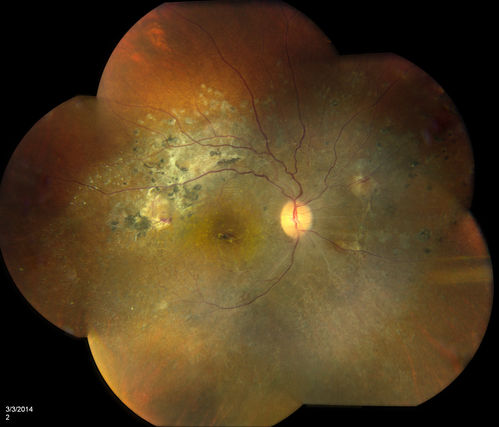

Lupus Retinopathy

Female patient comes in for eval on Lupus Retinopathy. Has poor vision in the right eye. VA is hand motion in the right eye. Fundus photos show fibrosis along the temporal arcades and narrowing of the arteries. No macular edema found.